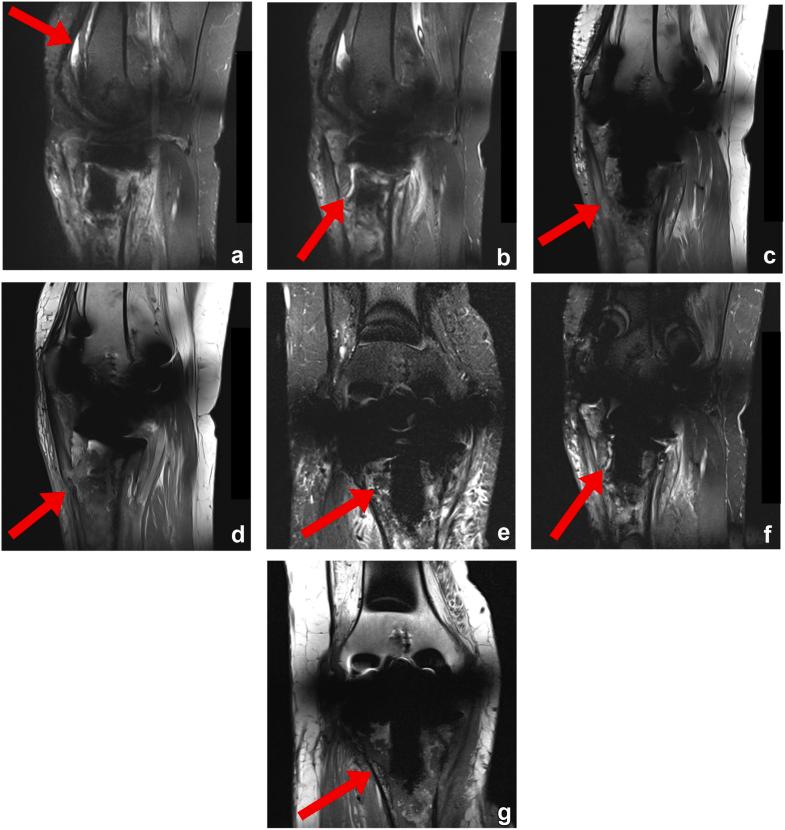

A 51-year-old woman suffered cardiac arrest requiring emergent intraosseous access that abutted the tibial component of her total knee arthroplasty. She developed a wound at the site and knee pain which was concerning for deep infection. Subsequent imaging was consistent with osteonecrosis developing around the tibial component. The component eventually loosened, requiring a revision surgery. Her deep cultures remained negative throughout. Her findings are most consistent with osteonecrosis and aseptic loosening of her prosthesis. While intraosseous access may be beneficial during resuscitation, it has complications. This is the first reported case of osteonecrosis secondary to intraosseous access leading to prosthetic loosening necessitating a revision surgery.

一名51岁女性发生心脏骤停,需要紧急进行骨内通路穿刺,穿刺部位紧邻其全膝关节置换术的胫骨部件。她在该部位出现了伤口和膝关节疼痛,令人担心发生深部感染。后续影像学检查结果与胫骨部件周围发生的骨坏死相符。该部件最终松动,需要进行翻修手术。她的深部培养物始终呈阴性。她的检查结果最符合假体的骨坏死和无菌性松动。虽然骨内通路在复苏过程中可能有益,但也存在并发症。这是首例报告的因骨内通路继发骨坏死导致假体松动并需要翻修手术的病例。